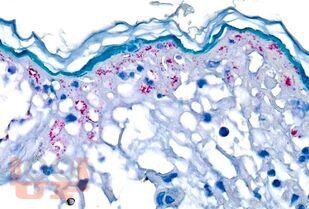

В учебном пособии представлены современные сведения об этиологии, эпидемиологии, основных аспектах патогенеза, клинических проявлениях, диагностике, дифференциальной диагностике, лечении и профилактике энтеровирусных неполиомиелитных инфекций.